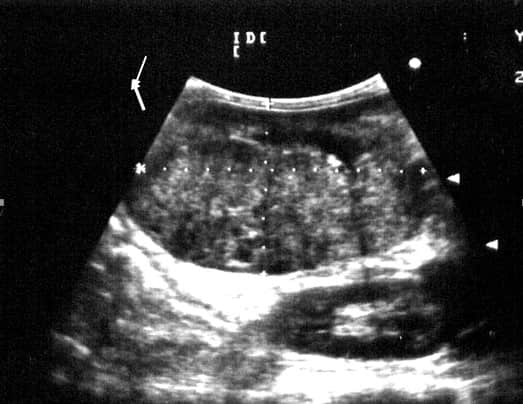

图5、左侧肋弓后方纵向扫查声像图显示左肾(大箭头)与右肾(小箭头)相比,左肾明显增大,左肾被膜光滑,内部的正常结构消失,呈高低相间的混响回声。

图6左侧肋弓后方纵向扫查声像图显示左肾被膜完整光滑,内部的正常结构消失,呈高低相间的混响回声。

通过X光拍片和B超联合检查可以诊断该犬患有肾脏肿瘤。